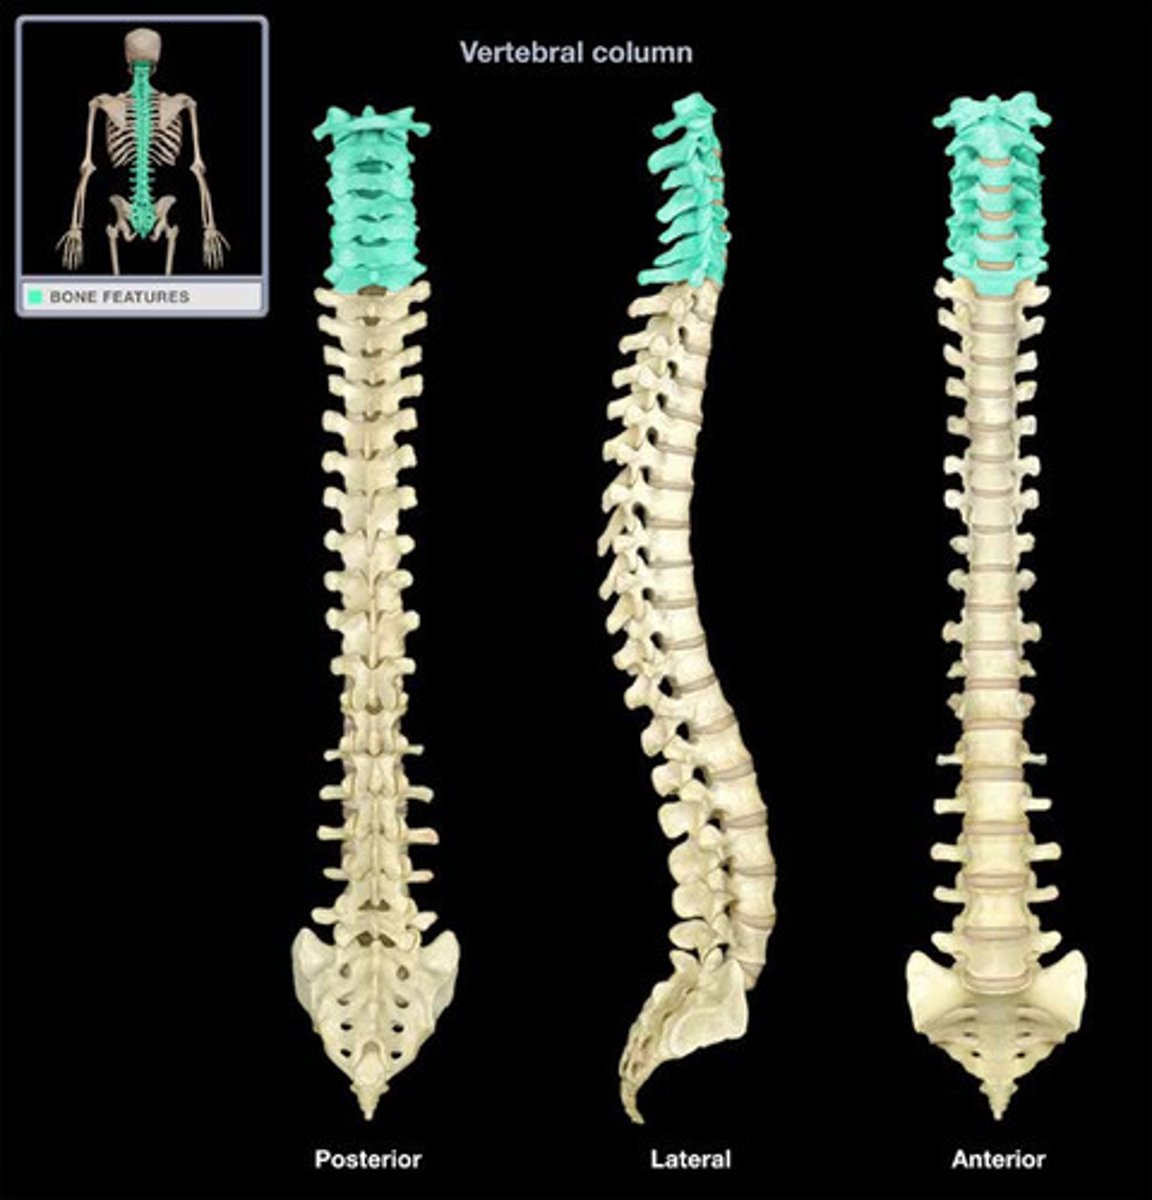

What are the sections of the vertebral column?

cervical, thoracic, lumbar, sacrum, coccyx

How many vertebrae make up the cervical spine?

7

How many vertebrae make up the thoracic spine?

12

How many vertebrae make up the lumbar spine?

5

How many vertebrae make up the sacral spine?

5 fused to form 1

How many vertebrae make up the coccyx spine?

3 to 5 fused to form 1

Which regions of the spine have CONCAVE curvatures and are described as LORDOTIC?

cervical and lumbar

Which regions of the spine have CONVEX curvatures and are described as KYPHOTIC?

thoracic and sacral